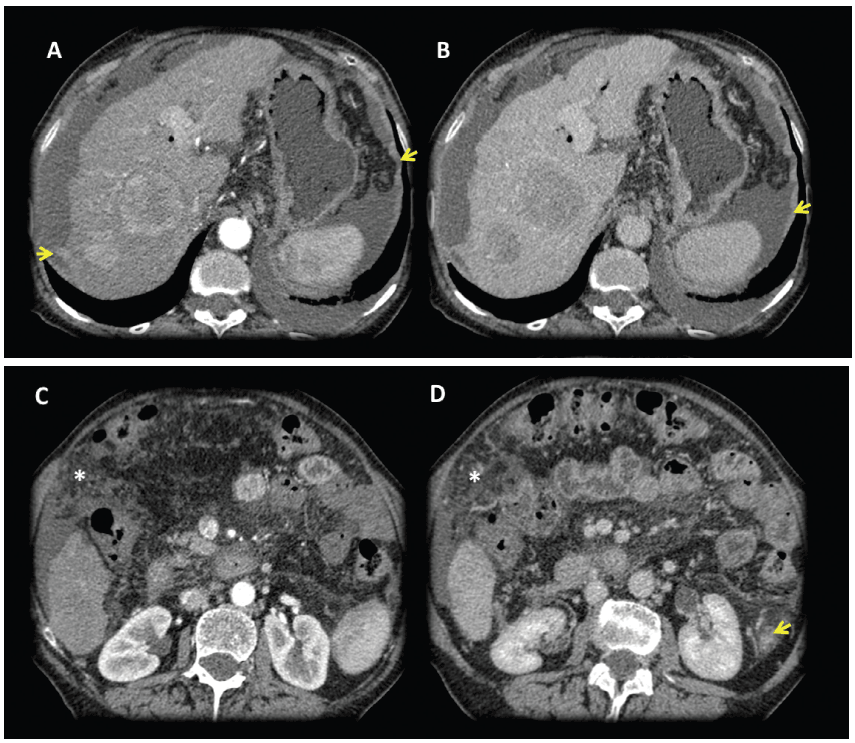

Contrast enhanced MDCT axial slices with arterial and portal-venous phase: Images shows a dysmorfic liver with severe portal hypertension and two hepatic lesions in the right lobe with early arterial enhancement with classical washout in portal venous phase, findings consistent with hepatocarcinomas (HCC). Tiny supramesocolic omental nodules (*) and peritoneal pseudonodular thickening that shows enhancement (arrows), findings that represents the peritoneal involvement. Small implant in the hepatic serosal surface in the right lobe (arrow).